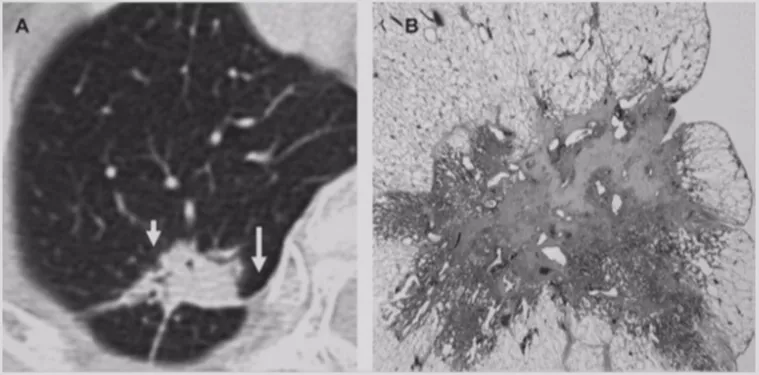

局灶性机化性肺炎

机化性肺炎有一个特点,它会有动态变化,大小和形态都有很大的变异,形态不规则呈多角形,贴近胸膜面(可有局限性胸腔积液)或沿支气管血管束分布,有粗长毛刺、尖角、向心性弓形凹陷、支气管扩张,部分病灶中心可出现低密度区(增强时呈周围强化),部分病灶边缘可见肺泡隔增厚而使边缘清晰,纵膈、肺门淋巴结增大较少见。

多灶性COP

多灶性机化性肺炎也可以表现为胸膜下或支气管周围的磨玻璃密度片影伴实变,支气管或细支气管周围边界不清的磨玻璃密度小结节,大的结节和肿块,反Halo征。因此,大家在做肺结节鉴别诊断的时候一定要考虑到该疾病。